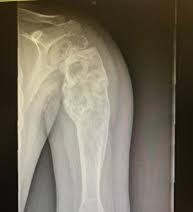

1. Rayos X

El diagnóstico de los sarcomas óseos se basa en los siguientes exámenes: Historial médico y exámenes clínicos

Examen radiológico.

Se usa una amplia gama de técnicas de adquisición de imágenes para poder ver dentro del cuerpo y determinar el alcance de un sarcoma óseo y establecer la presencia o ausencia de enfermedad metastásica distante.